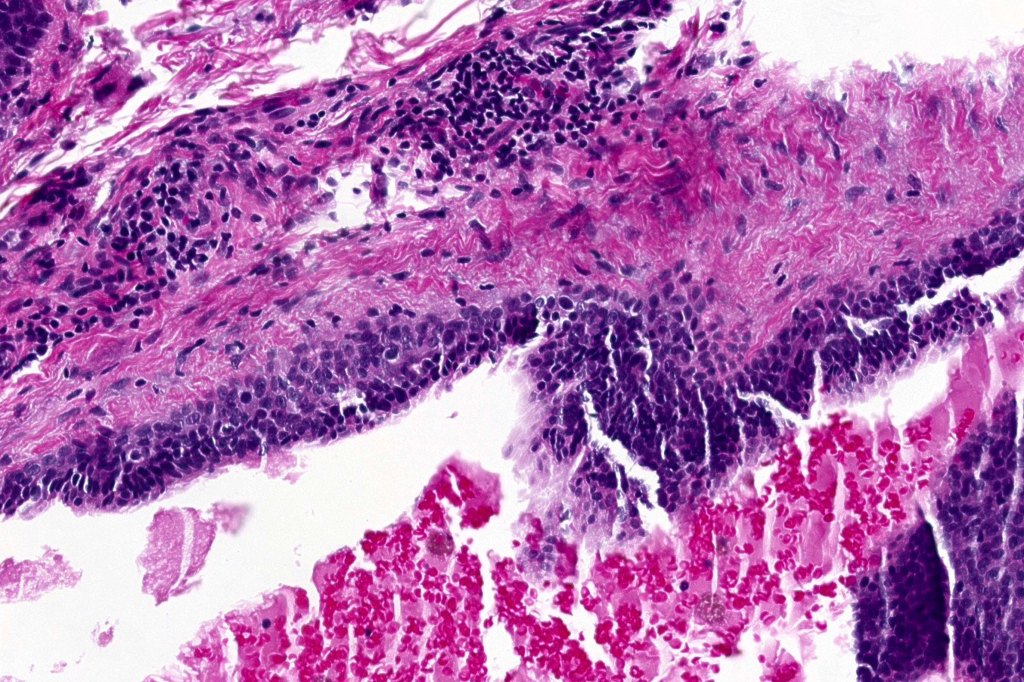

Histological features

•Pseudo-encapsulated unilocular or multilocular

•Outer myoepithelial cells & inner layer of columnar cells with eosinophilic cytoplasm showing decapitation secretion

•Adenomatous/papillary component (cystadenoma)